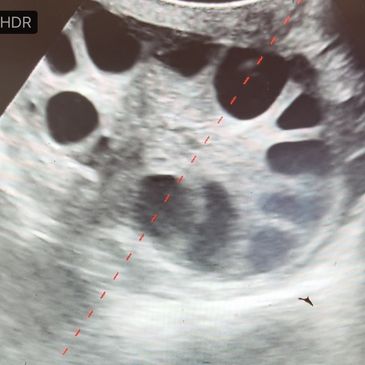

Donors are stimulated with FSH to create a uniform population of follicles. Timing of FSH administration and ovum pick-up (OPU) collection are optimized to allow oocytes to be ready for fertilization when they reach the lab.

An OPU probe contains an ultrasound and needle guide, so that the ovary can be visualized then stabilized for aspiration.

A needle is guided through the OPU probe and follicles on the ovary are individually penetrated. The follicle contains both follicular fluid and an oocyte. Similar to embryos, the oocyte is too small to see with a naked eye.